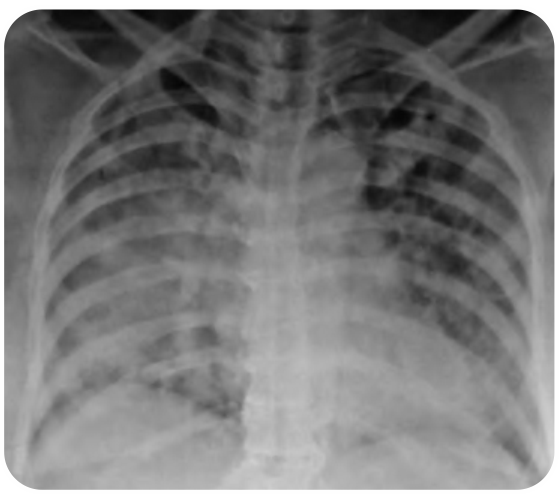

Case 8 -Young Boy Presenting with Breathlessness

Click here to view